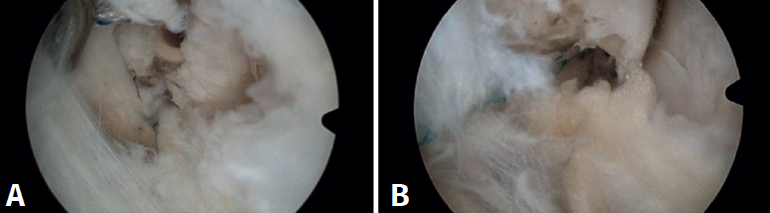

Hubo 3 pacientes (1%) con intolerancia a la sutura, que requirieron cirugía abierta (Figura 3). Tuvimos 2 casos (0,5%) de fracturas maleolares no desplazadas, una del maléolo medial y otra del maléolo peroneo, ocurridas durante la colocación del arpón en la reparación ligamentosa (Figura 4). Ninguno de estos pacientes requirió intervención adicional y fueron tratados con inmovilización durante 4 semanas, continuando con el protocolo de rehabilitación posterior. En otro caso (0,26%), se observó la migración del arpón hacia la parte posterior del peroné (Figura 5), diagnosticada a los 3 meses tras la cirugía; se decidió conducta expectante dada la ausencia de síntomas.